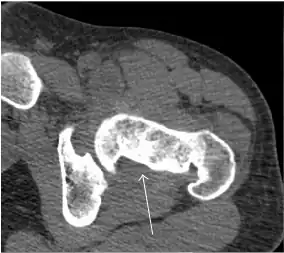

Synovial chondromatosis can be confidently diagnosed by X-ray when calcified cartilaginous chondromas are seen. However, other synovial proliferative processes, such as pigmented villonodular synovitis, require MRI for accurate diagnosis, although noncalcified synovitis can be suspected in radiographs by indirect signs, such as soft tissue swelling and/or erosions in the femoral head, femoral neck, or acetabulum (Figure 7).[1]

Figure 7:

Axial CT image of pigmented villonodular synovitis eroding the posterior cortex of the femoral neck.[1] -

Sagittal T2* gradient echo image showing a posterior soft tissue mass with hypointense areas secondary to hemosiderin deposition.[1] -

X-ray of synovial chondromatosis.[1] -

CT of synovial chondromatosis.[1]

In synovial proliferative disorders, MRI demonstrates synovial hypertrophy. In the case of PVNS, characteristic foci of low signal intensity related to hemosiderin deposition are better seen on gradient echo T2* images (Figure 7). In the case of synovial osteochondromatosis, the synovial hypertrophy is accompanied by intermediate signal cartilaginous loose bodies and/or low signal calcified loose bodies.[1]